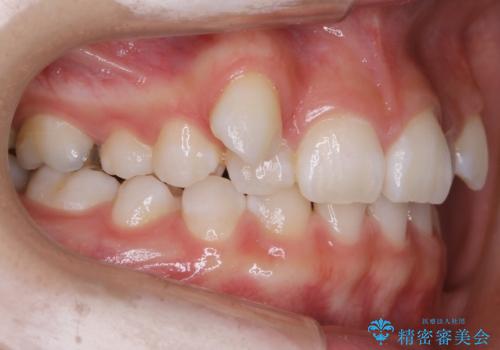

- 歯のガタつきを主訴にご来院されました。

ガタつきがあるだけでなく、元々永久歯が欠損している「先天欠如」で歯の本数が少なく噛み合わせ等も治療する必要がありました。

かなり特殊な状況からの矯正治療になるため抜歯する本数や位置、並んだあとのスペースのコントロールを慎重に計画し、マウスピース装置のインビザラインで治療を開始しました。